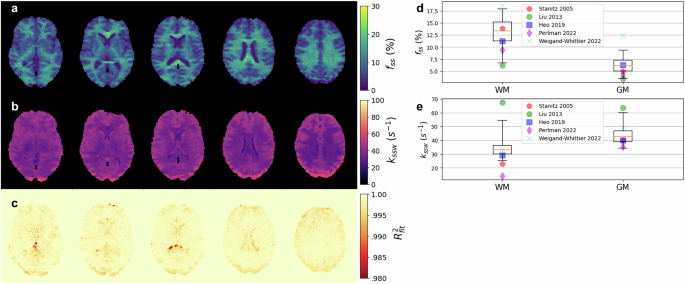

Quantitative semisolid-MT and amide proton exchange parameter maps derived from a representative healthy volunteer are presented in Fig. 3 and Fig. 4, respectively. The resulting proton volume fractions and exchange rates were in agreement with the literature (although the large variability in previous reports is noted; see Fig. 3d, e and Fig. 4d, e). The mean values obtained for white/gray matter (WM/GM) were: fss = 13.09 ± 3.44(%), kssw = 34.7 ± 7.8(s−1), fs = 0.33 ± 0.08(%), ksw = 305.1 ± 34.0(s−1) for white matter and fss = 6.28 ± 1.88(%), kssw = 44.2 ± 7.5(s−1), fs = 0.21 ± 0.06(%), ksw = 235.9 ± 46.0(s−1) for gray matter.

Results of neural Bloch-McConnell fitting (NBMF)-based quantification of the MT-related tissue parameters in the human brain scanned with a pulsed MT Magnetic Resonance Fingerprinting (MT-MRF) protocol are presented. Representative reconstructed parameter maps of the semisolid-MT proton volume fraction (a) and proton exchange rate (b), alongside a fidelity estimation (c) of the data-model agreement, computed as R2 = 1-NMSE (normalized mean square error). d, e Statistical analysis of the resulting proton exchange parameter values across the brain white matter and gray matter (WM/GM) regions of interest (box-plots, n=47,442/64,611 voxels, respectively), compared to literature (colored markers)12,43,45,90,91. In the boxplots, the central horizontal lines represent median values, box size represents the two central (2nd, 3rd) quartiles, the whiskers represent the 90 central percentiles, and outliers are omitted.